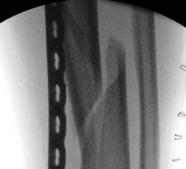

Nail Insertion and Distal Interlocking

Following meticulous preparation, the canal is reamed sequentially. Care must be taken not to over-ream the distal segment, which could compromise the already tenuous metaphyseal bone stock. The nail is inserted gently; forceful impaction is strictly avoided to prevent displacing the previously secured articular block.

Image

Distal interlocking must be maximized. The surgeon should utilize a minimum of three, and ideally four, distal locking screws, engaging the bone in multiple planes (e.g., two medial-to-lateral, one anterior-to-posterior). This multi-planar fixation is essential to control rotation and angular displacement in the wide metaphyseal bone.